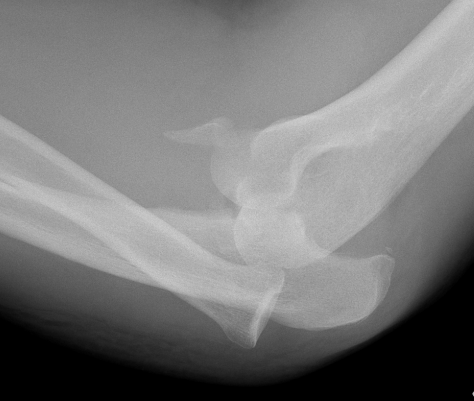

Elbow dislocation with radial head fracture

Management

Critical to elbow stability

Based upon Mason classfication